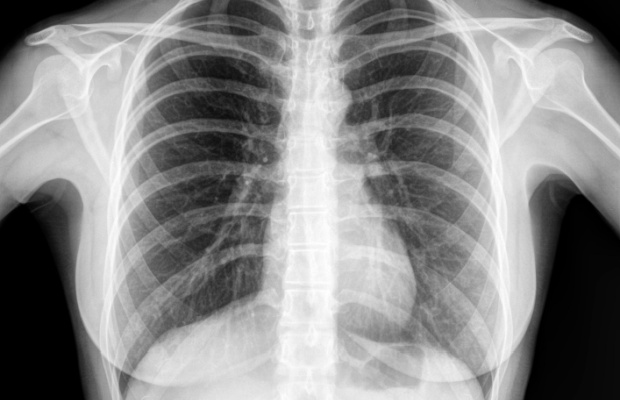

Tests are used to diagnose a heart condition or to see how healthy your heart is. Find out what to expect from some of the most common tests.